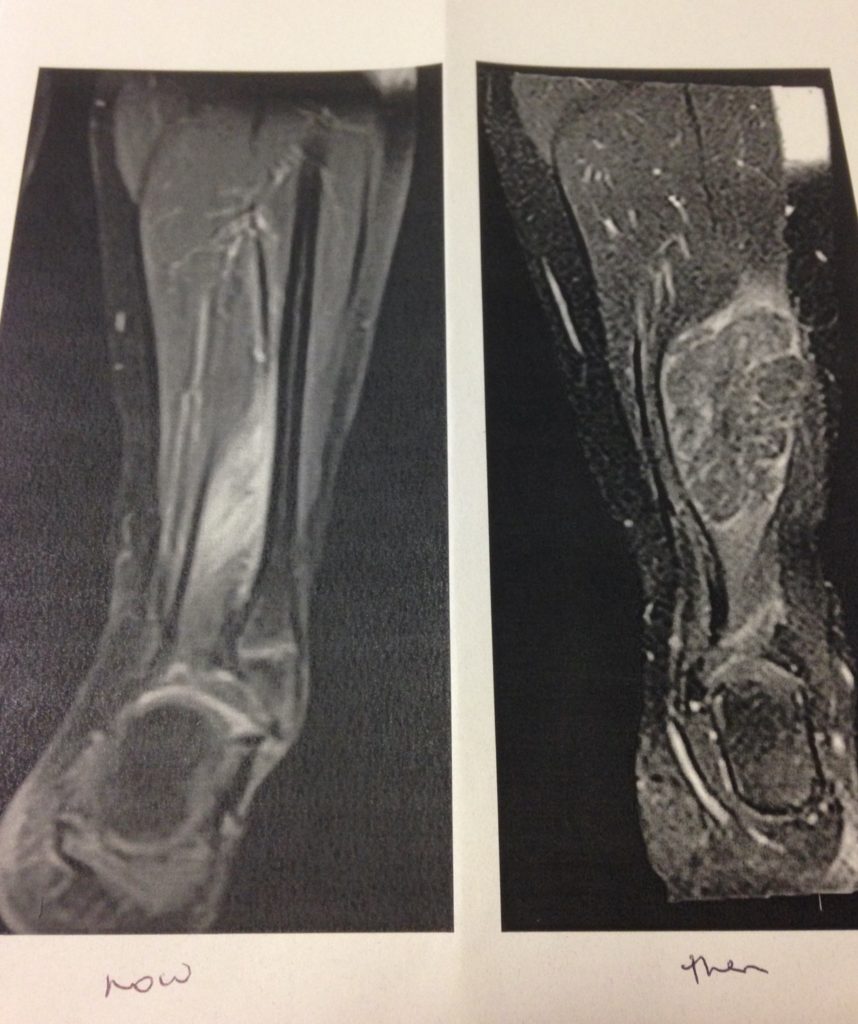

Rhabdomyosarcoma – Be More Ruby

bemoreruby.com

bemoreruby.com

rhabdomyosarcoma ruby leg diagnosis cycles right